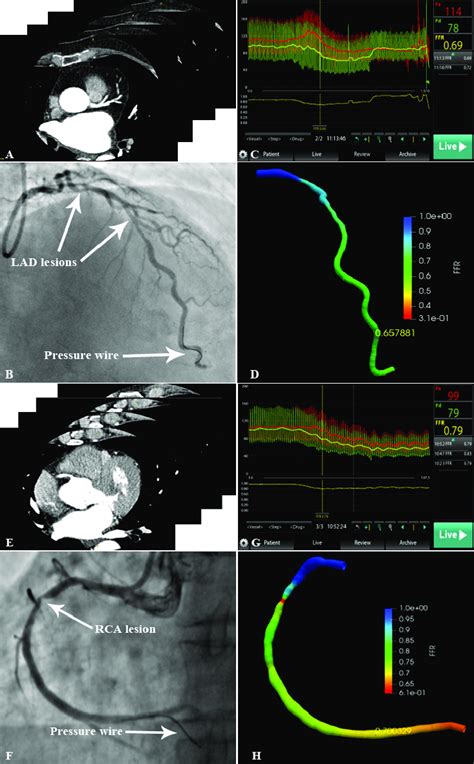

So, what exactly is FFR CT, and why should you even care about its cost? Think of FFR CT as a super-smart, non-invasive way to look at your heart’s blood vessels. FFR CT stands for Fractional Flow Reserve computed tomography . Traditionally, if doctors suspected a significant blockage in your coronary arteries that was impacting blood flow, they might have recommended a cardiac catheterization. This involves inserting a thin tube (a catheter) into an artery, usually in your groin or arm, and guiding it up to your heart. Then, they inject dye and take X-rays. To measure the actual impact of a blockage on blood flow, they would insert a tiny wire through the catheter into the blocked artery during the procedure itself. This is called measuring FFR (Fractional Flow Reserve) invasively. It’s accurate, but it’s also an invasive procedure , meaning it involves inserting instruments into your body, carrying some risks like bleeding, infection, or even heart attack (though rare). FFR CT changes the game! Instead of going through all that, doctors can now get a similar, often equivalent, assessment of blood flow using a standard CT scan. This revolutionary technique uses advanced computational fluid dynamics and AI algorithms to analyze a regular CT angiogram (a scan that visualizes your coronary arteries). It essentially creates a 3D model of your heart and vessels and simulates blood flow through them, calculating the FFR value without needing to go inside your body. This means fewer risks, less discomfort, and a quicker recovery for you, guys. The value it brings is immense: it can help doctors decide more accurately whether you need an intervention like stenting or bypass surgery, or if medication is sufficient. This precision can lead to better patient outcomes and potentially avoid unnecessary procedures. And that’s exactly why understanding its cost is so crucial – it’s a step towards more personalized and less invasive cardiac care.